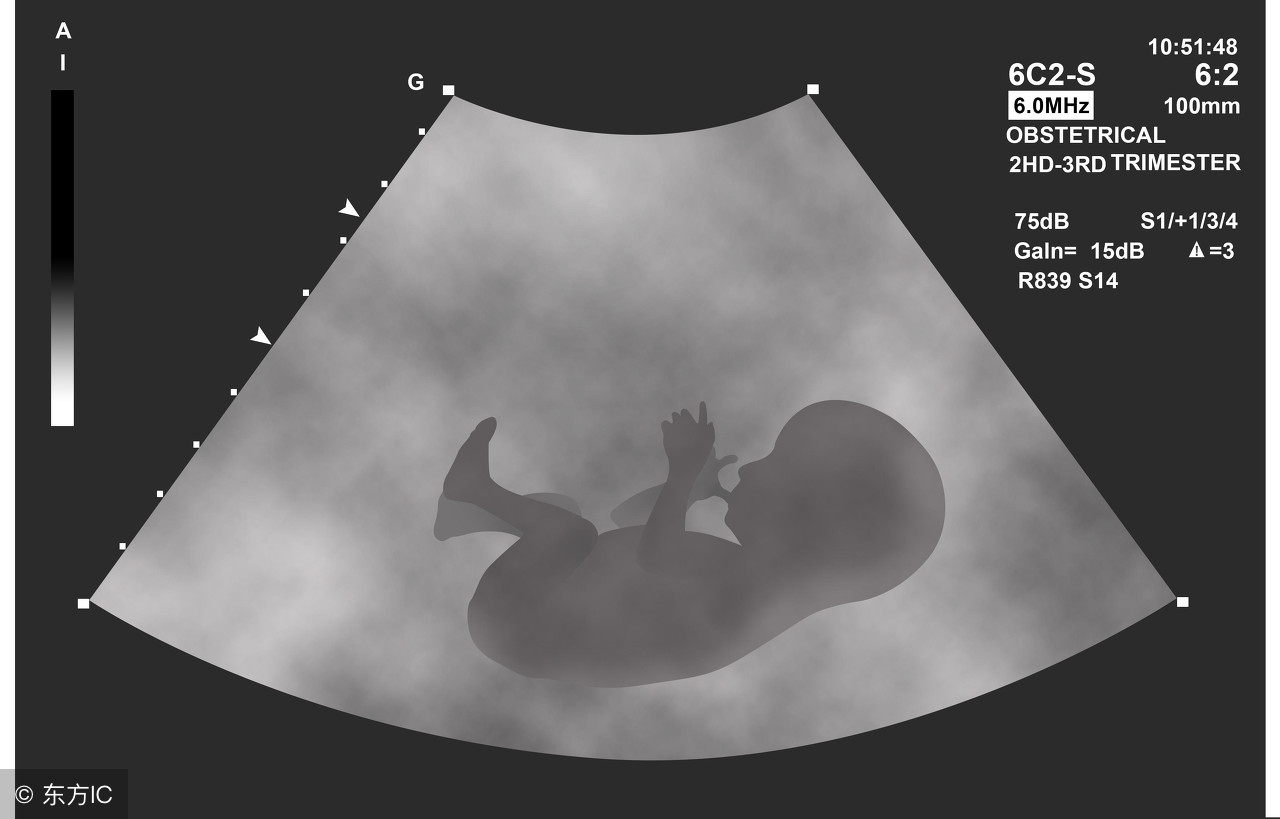

B超检查胎心胎芽,100-150元(有的地方B超要200元以上)

B超检查,NT检查,100-300元(青岛、河南等地,NT也是免费的)

B超检查,100-150元

B超,100-150元